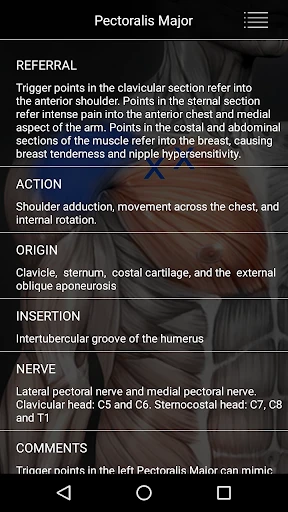

The app launches you into a detailed map of the human body, highlighting key muscle groups and their potential trigger points. This is perfect for anyone keen on learning more about their anatomy, whether you’re a seasoned athlete or just someone looking to relieve some tension. The interface is clean and intuitive, making it easy to navigate through the complex web of musculature.

What I really enjoyed about this app is the interactive element. You can tap on different muscle groups to see common trigger points, and it provides detailed descriptions of each. This isn’t just a static anatomy chart; it’s like having a mini anatomy lesson in your pocket. Plus, the app includes helpful tips on how to alleviate discomfort in these areas, which I found quite practical.

While this app is a great tool for anyone interested in muscle health, it’s especially useful for athletes, physiotherapists, and fitness enthusiasts. If you’re someone who frequently deals with muscle pain or stiffness, this could be your go-to resource. Even if you’re not an expert, the app does a great job of breaking down complex information into digestible bits.